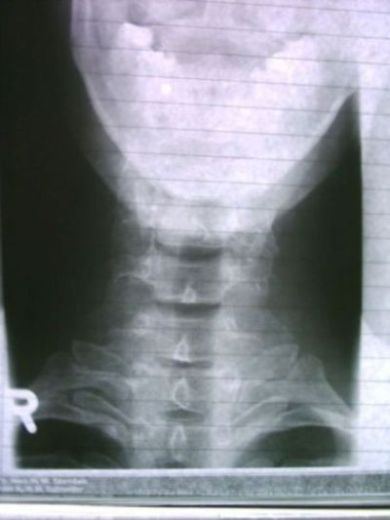

Spondylolisthesis (Wirbelgleiten)

Abgleiten eines Wirbelkörpers nach vorn.

Dabei kann sich ein einzelner Wirbelkörper "wie eine Schublade" aus dem normalen Gefüge der Wirbelsäule lösen.

Normalerweise nicht selten in der LWS. Habe aber schon gehört und gelesen, daß das auch in der HWS vorkommen kann.

Die Aufrichtung im Korsett hat über die starke Begradigung der LWS und BWS eine Bogenschlußstörung (Disharmonie der sagitalen Krümmungen der WS) ausgelöst. Du musst Dir das so vorstellen. Deine LWS-lordose und Deine BWS-Kyphose waren zwar zu stark, aber sie bildeten trotzdem zusammen mit der HWS-Lordose eine in den "Krümmungs-Kurven" relativ harmonische Einheit.

Diese Harmonie wurde durch das stark aufrichtende Korsett gewaltig gestört. Die LWS-lordose und BWS-kyphose wurden dramatisch begradigt, die HWS Hyperlordose blieb aber so, wie sie es seit jahren/jahrzehnten gewohnt war. Das bildete am BWS-HWS Übergang eine Zone der Spannung und Überreizung durch das "Knick-Moment".